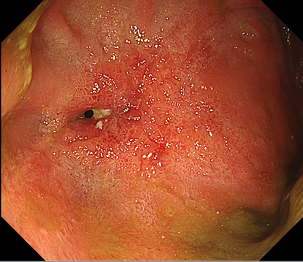

消化管の狭くなっている部分に対してバルーン(風船)を用いて広げる治療になります。

主な対象疾患としては、術後吻合部狭窄や炎症性腸疾患(IBD)炎症瘢痕狭窄などの良性狭窄になります。